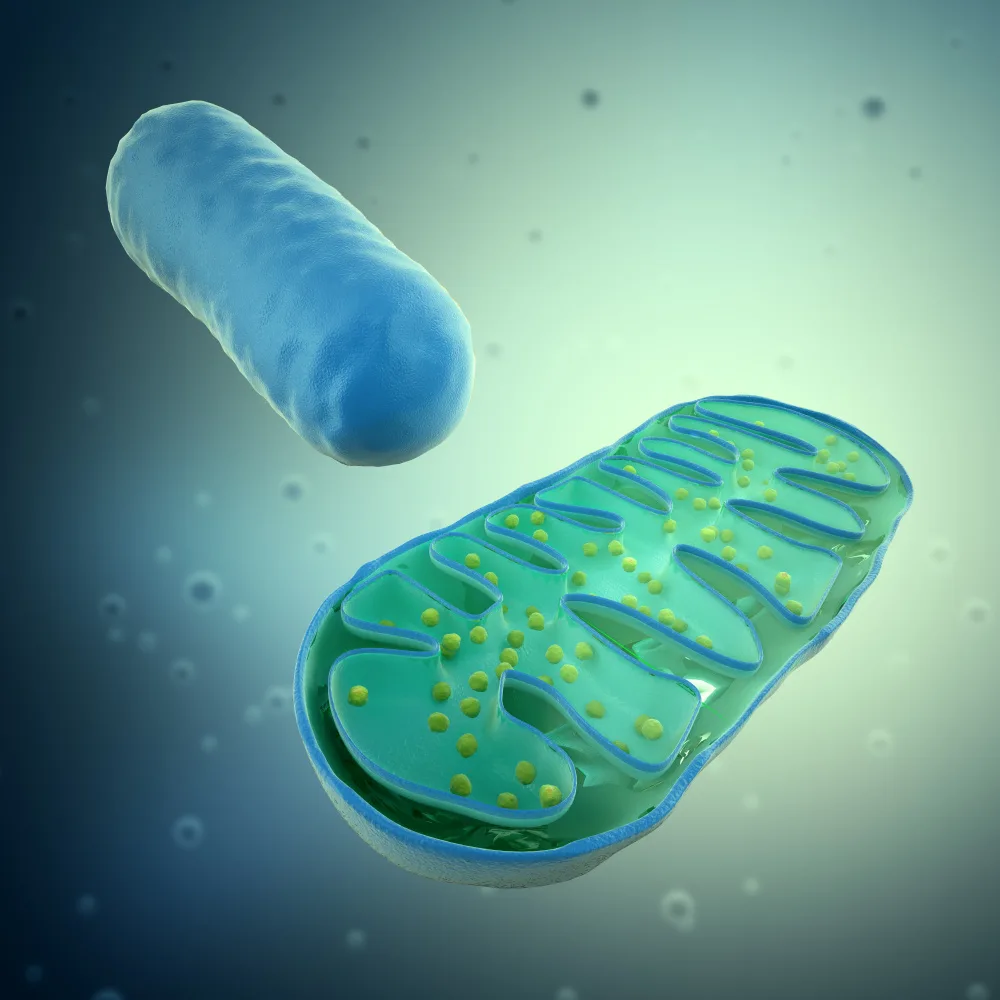

Circulation and Mitochondrial Dysfunction

Circulation and Mitochondrial Dysfunction Presented by Merrill K Galera, MD Learn to identify at-risk patients, understand the mechanisms of circulation...

The Critical Role of Mitochondria and DesBio’s Innovative Solutions

Promoting Total-Body Health: The Critical Role of Mitochondria DesBio's Innovative Solutions for Cellular Energy Support Explore how mitochondrial health...